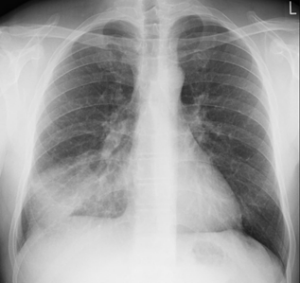

Le diagnostic est confirmé par la radiographie pulmonaire.

antibioest nl radiographie pulmonaire